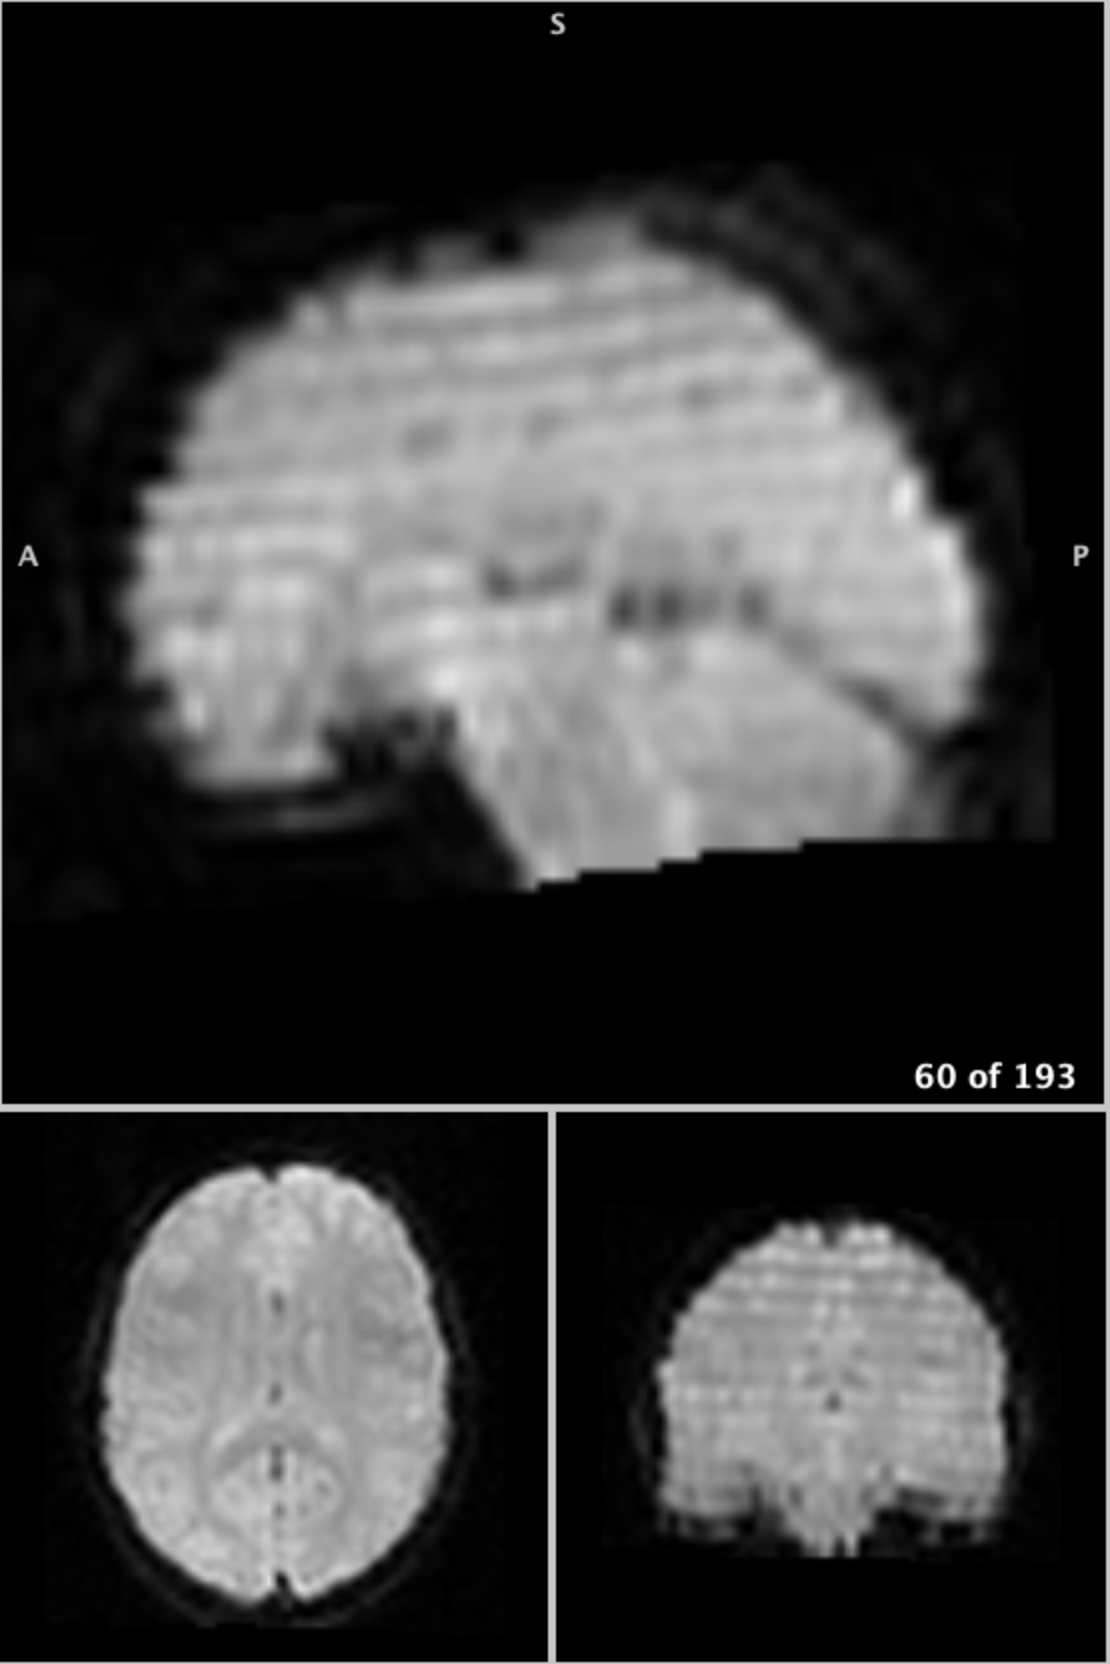

Figure 9 shows Normal Q-Q plots for the first principal component for each subject before and after SHASH transformation. The distribution for subject 1 exhibits light tails prior to transformation, while the distribution for subject 2 is slightly right-skewed. While several points clearly deviate from the bulk of the distribution prior to SHASH transformation, none exceed the outlier detection threshold of , indicated by the grey band. By contrast, after transformation several observations are identified as outliers. The most extreme outlier in PC1 is volume 60 of subject 1, which is visualized in Figure 10 along with several neighboring volumes. Its immediately preceding neighbor is also detected as an outlier, while a slightly earlier volume is not. A banding artifact consistent with head motion is clearly seen in the two outlying volumes, while no such abnormalities are seen in the non-outlying volume.

| Volume 56 | Volume 59 | Volume 60 | ||

![]() |

||